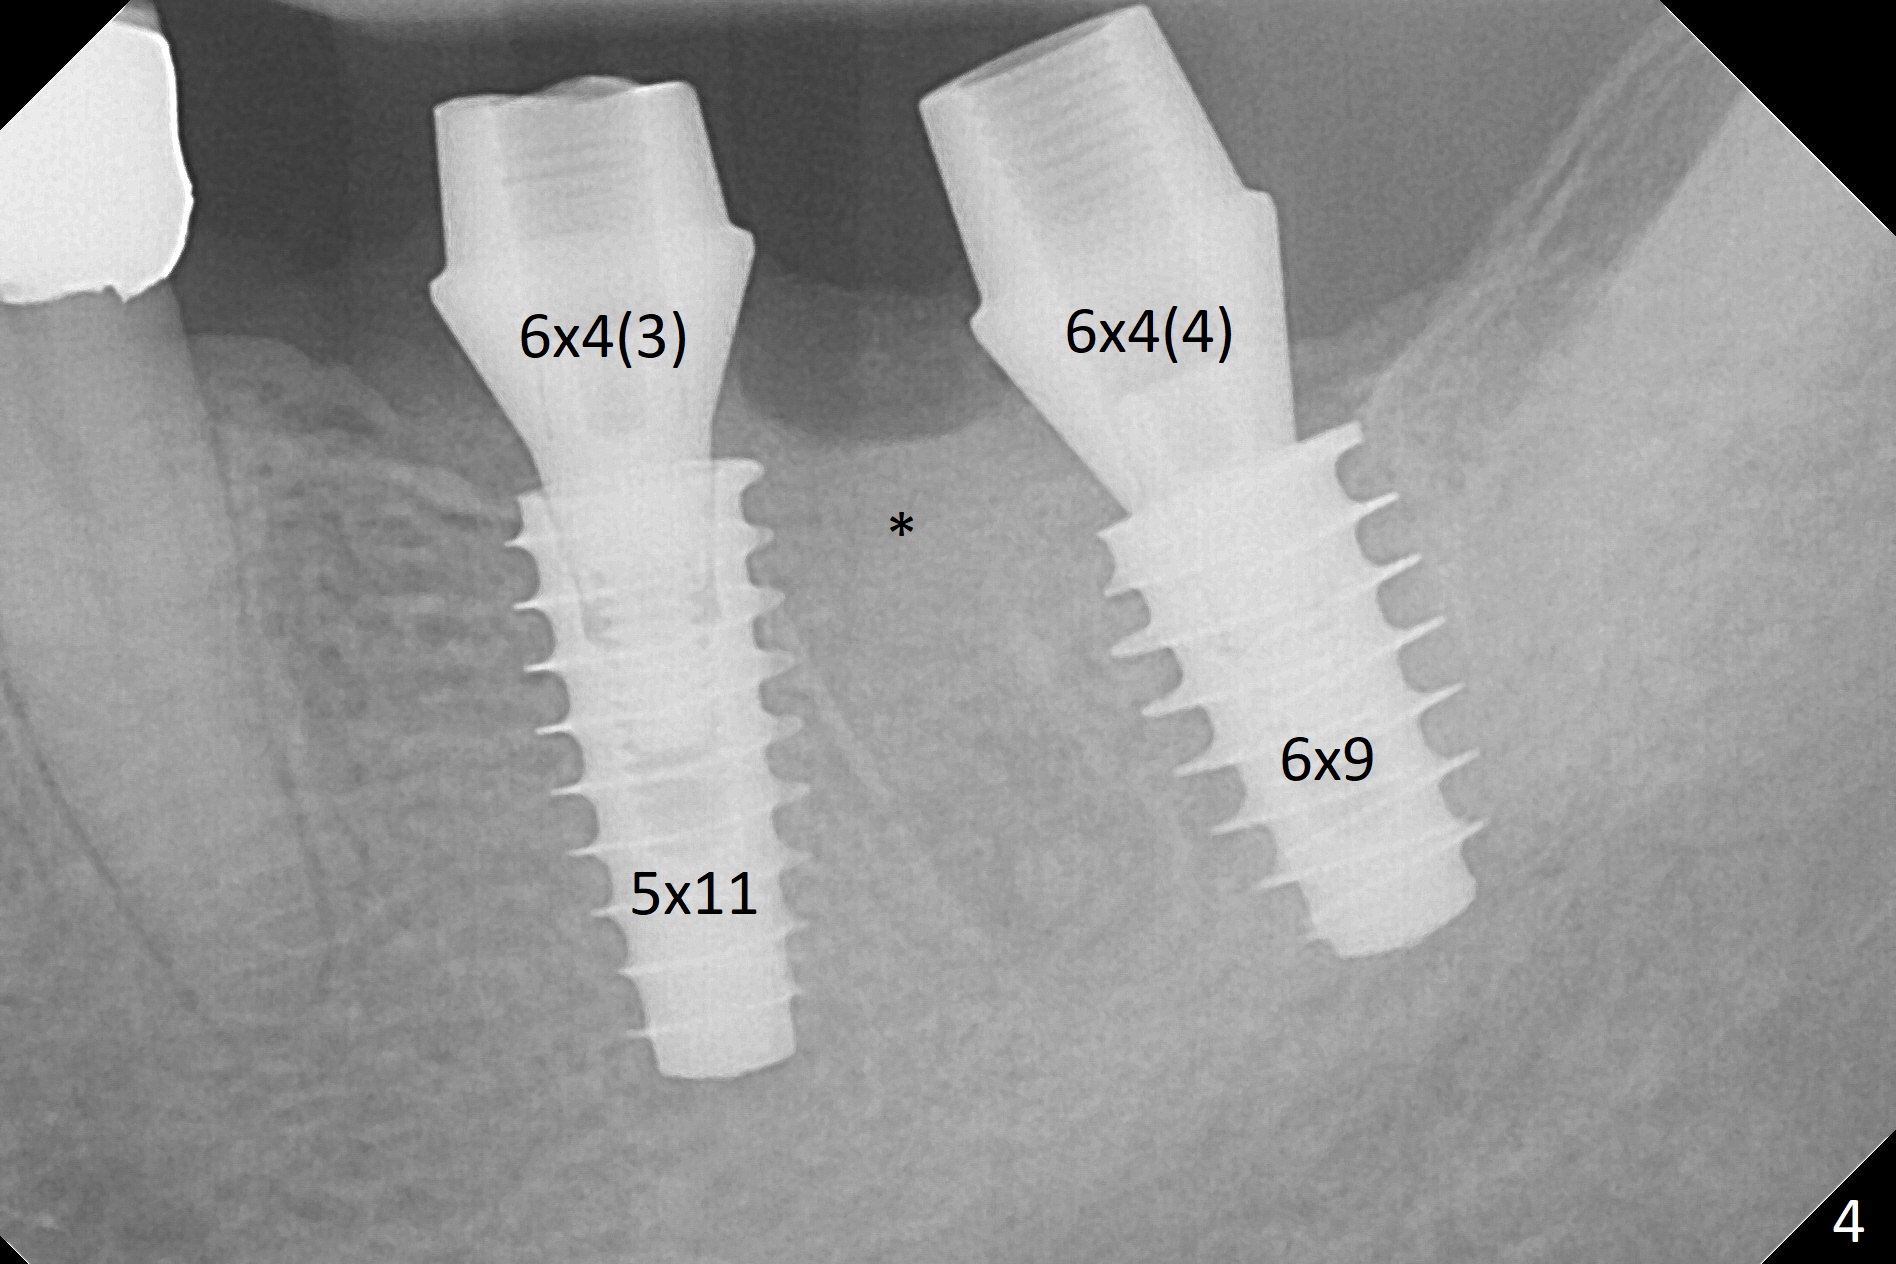

After extraction of the residual root at #18 (Fig.1), the septum is narrow, while the distal socket seems to be the most appropriate site for implant placement (Fig.2 (M: mesial)). In fact the implant needs to tilt slightly distally (relative to the original trajectory of the distal socket, Fig.3 green) to occlude with the opposing tooth. The implant at #19 could be placed more mesially (Fig.4 (*: Vera Graft)).

A drawback of placing an implant in the distal socket of the 2nd lower molar is closer to the Inferior Alveolar Canal. The implants seem to have osteointegrated 4.5 months postop (Fig.5). While the ridge at #19 appears to be wider than preop (as compared to Fig.1), that at #18 seems to be atrophic 5 months postop (Fig.6 * (1 week post cementation)). The distal implant placement at #19 may increase possibility of abutment screw loosening during functioning (Fig.7 *). When the patient returns for periodic exam 1.5 months post cementation, loose contact between the implant crowns is noted (Fig.8). The bony trabeculae form between the 2 implants crestally 12 months postop, i.e., 7 months post cementation (Fig.9). The loose contact between the 2 implants is corrected 14 months post cementation.